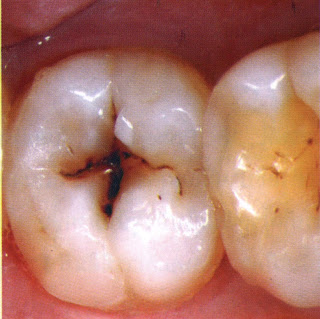

Karies Gigi atau gigi berlubang

Karies gigi merupakan masalah terbesar yang sering menyerang gigi. Untuk

mencegah agar gigi tidak berlubang, caranya harus menggosok gigi dengan benar

mengurangi konsumsi makanan yang terlalu manis, dan mengunakan pasta gigi yang

mengandung flouride.

Perhatian juga gigi kau satu per satu, apakah ada titik

hitam yang merupakan tanda dari karies gigi. Jika menemukan titik hitam pada

gigi, segera kedokter gigi, jangan tunggu sampai gigi terasa sakit, sehingga

karies gigi dapat dicegah dan gigi tidak perlu dicabut.